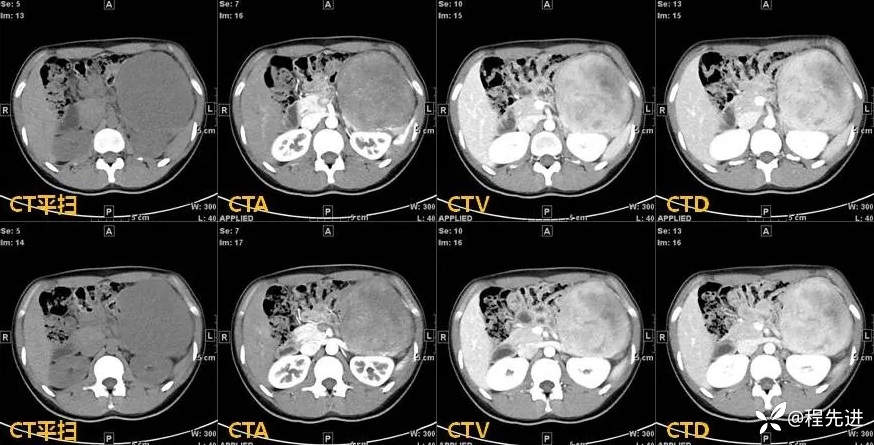

【现病史及既往史】:患者4天前于外院行CT检查发现胰腺肿物,胰胃间隙见一肿物,大小约108mmx103mmx122mm,考虑胰腺实性假乳头状瘤可能性大,无伴发热、畏寒,无恶心、反酸,无呕血、黑便。患者起病以来,一般情况可,无头晕、头痛,无心悸、气促,无腹泻、便秘,无排陶土样大便。精神可,胃纳、睡眠差,尿量如常,尿色淡黄,大便规律,体重未见明显改变。

影像检查: